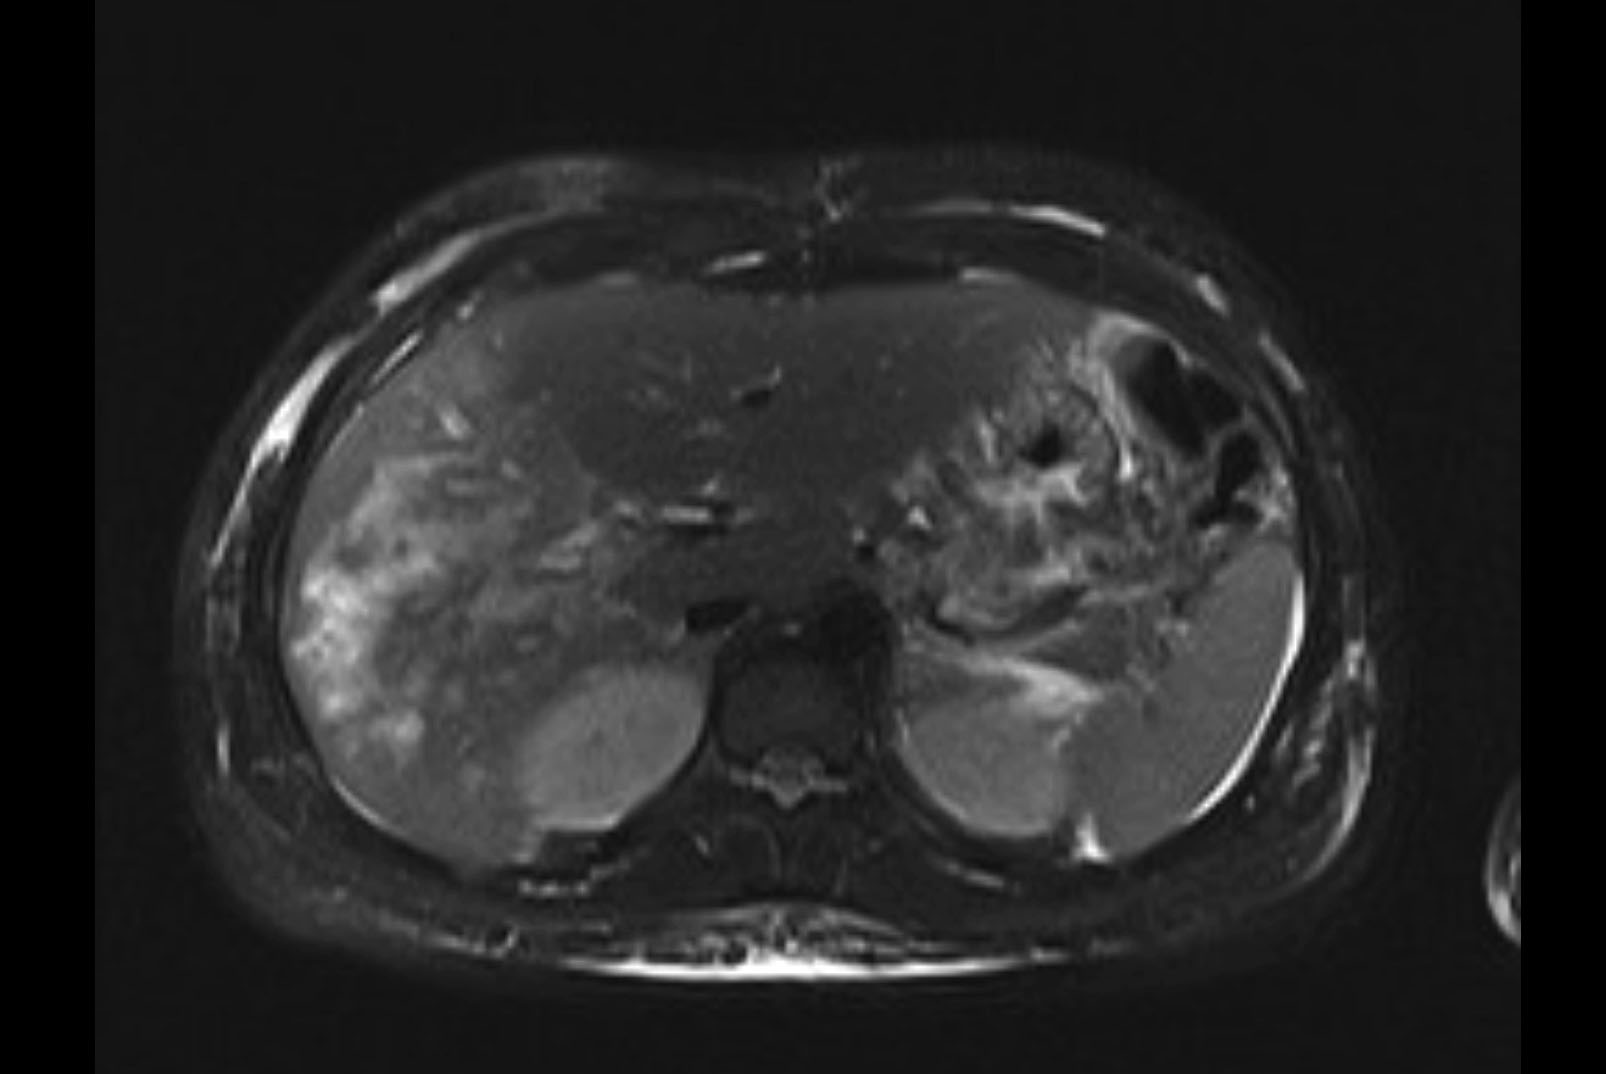

MRI T2

Imaging analysis

Based on initial findings, which issue(s) would you be most concerned about?